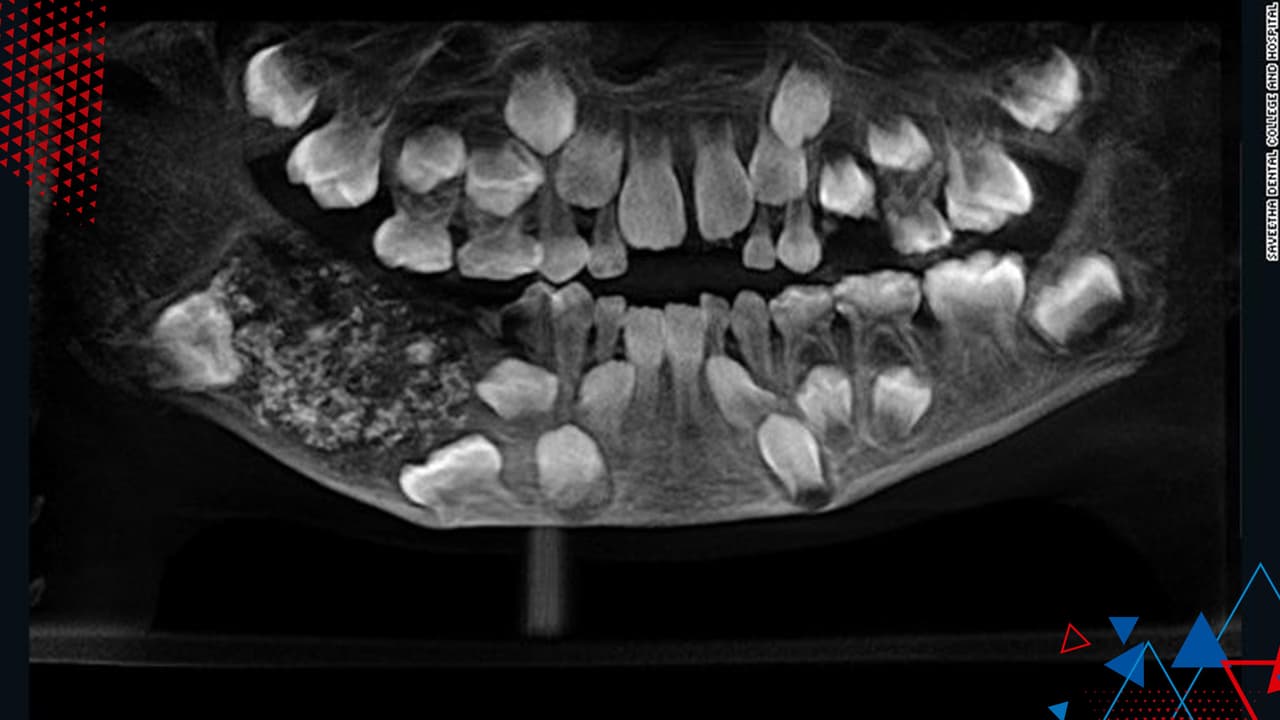

Al revisar la garganta, los médicos detectaron un objeto extraño que tapabas sus cuerdas vocales. Una nueva radiografía reveló el origen de su malestar: un puente metálico y tres dientes postizos se habían alojado en la parte superior de su garganta.